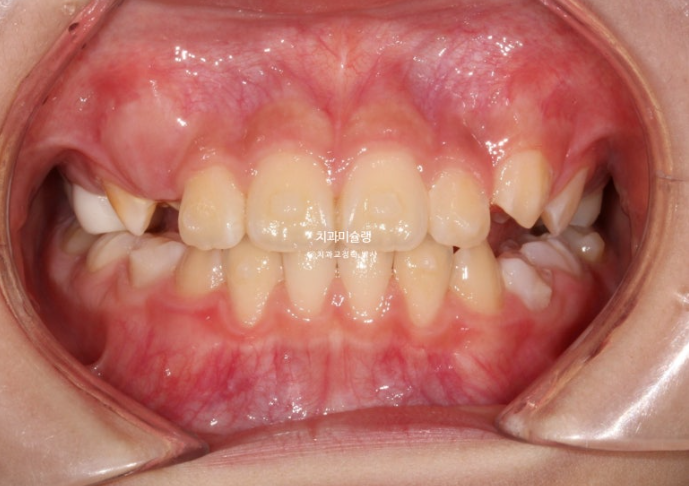

23년 10월 압구정 어린이 교정

교정치료를 위해 온 어린이 입니다.

23.10

윗니가 아랫니를 많이 덮어 아래 앞니가 안 보이는 과개교합이 있습니다.

중심선 불일치도 보입니다.

윗니 뻗침이 있어서 돌출을 느끼는 상태입니다.

앞니 위아래 4개씩 총 8개 영구치 앞니는 약간의 삐뚤함이 있지만 큰 공간부족 없이 잘 나온 편 입니다.